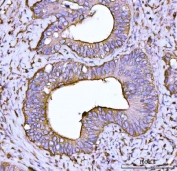

IHC staining of FFPE human prostate cancer tissue with ACTN4 antibody. HIER: boil tissue sections in pH8 EDTA for 20 min and allow to cool before testing.